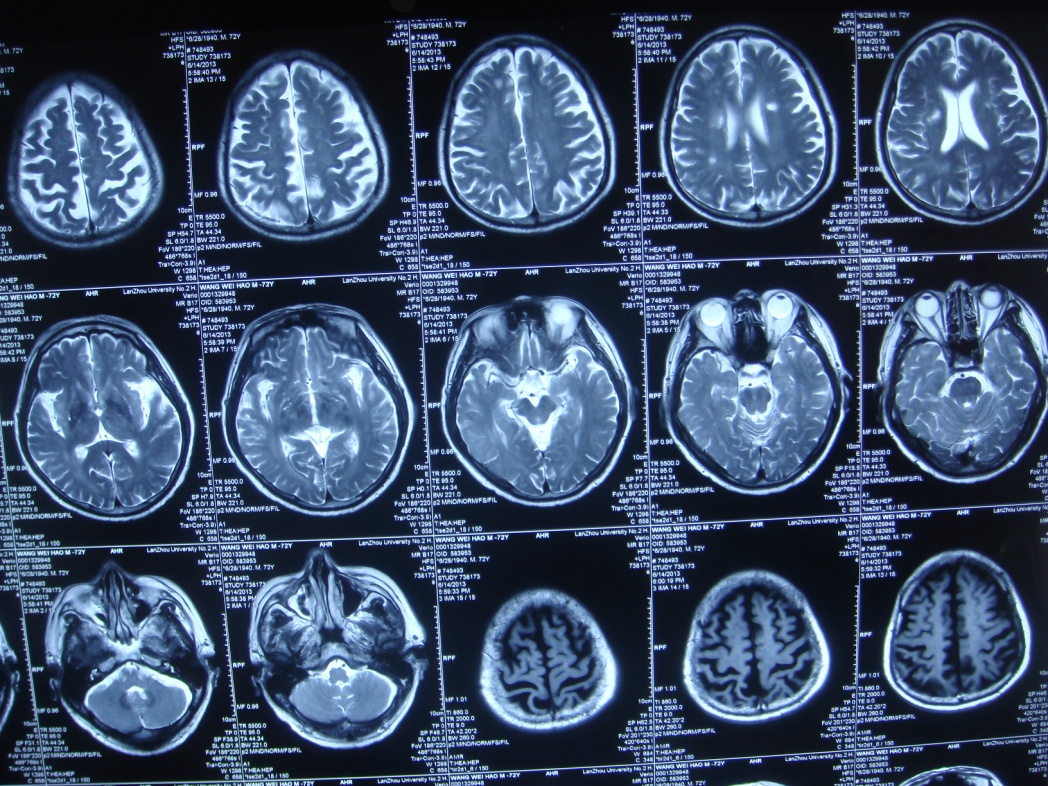

头部核磁显示颅内多发梗塞灶,以右侧为主。